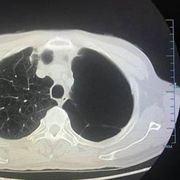

胸片是什么

胸片是影像学检查中的必备检查项目之一,因为其简单、方便操作的优势已经成为了日常临床工作中的首选检查。它可以帮助诊断出典型的肺部感染、肺结核以及肺部的...70250人收听

胸片怎么看

学会看胸片是临床医生必备的技能之一,首先,看胸壁的X线表现,观察胸壁软组织有大的肿块,有皮下积液、积气,同时观察肋骨的连续性是否有中断,这是肋骨骨折的X线征象...73227人收听

在临床上胸部X光片检查是常用的一种检查方法,它是利用X线产生图像,从而观察胸部的病变。胸片的观察需要按一定的顺序,一般可以按照从上往下的顺序,观察双肺上叶...1人收听

胸片就是普通x线胸部平片,一般都是拍胸部正位片。胸部正位片主要显示的是两侧的肺野,心影轮廓大小,胸椎,以及肋骨。作为影像科普通的检查,方便、快捷,为临床科室解决了许多常见的问题。比如...